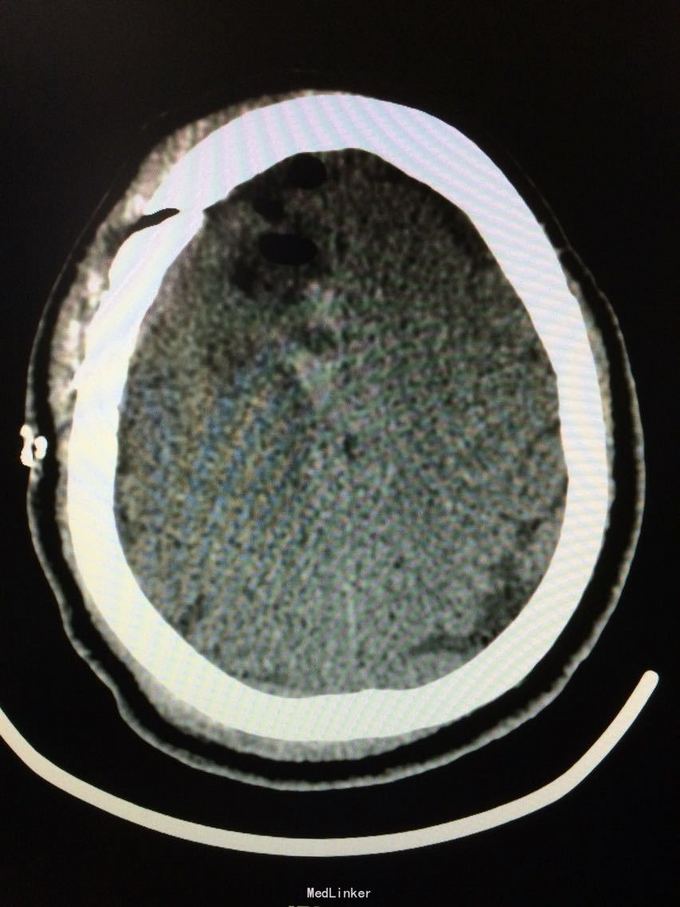

主诉:记忆力减退3月,左侧肢体乏力3天 病史:患者51岁女性,3月前无明显诱因出现记忆力减退,伴头痛,3天前出现站立不稳,左侧肢体乏力,步行困难,当地CT提示右侧额叶低密度灶,

查体:左侧上肢肌力4级,右侧5级,轻瘫试验左侧阳性 辅助检查:右侧额叶、胼胝体膝部病变伴出血,增强扫描明显强化。考虑胶质瘤

诊断:右侧额叶多发脑软化灶 处理:全麻下行右侧额叶占位病变切除术,术后病理提示:符合脑软化,未见明显肿瘤因素等